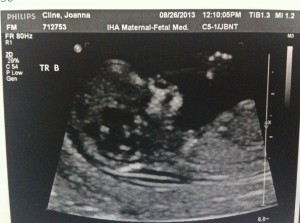

Good morning! I’m 10w1d today and we went for another ultrasound this morning. The u/s tech told us that everything looks exactly as she’d want it to at this point in the pregnancy. The heartbeats are great and they are wiggling around in there!

I’ve attached a few new photos – close ups of each and one group shot. 🙂